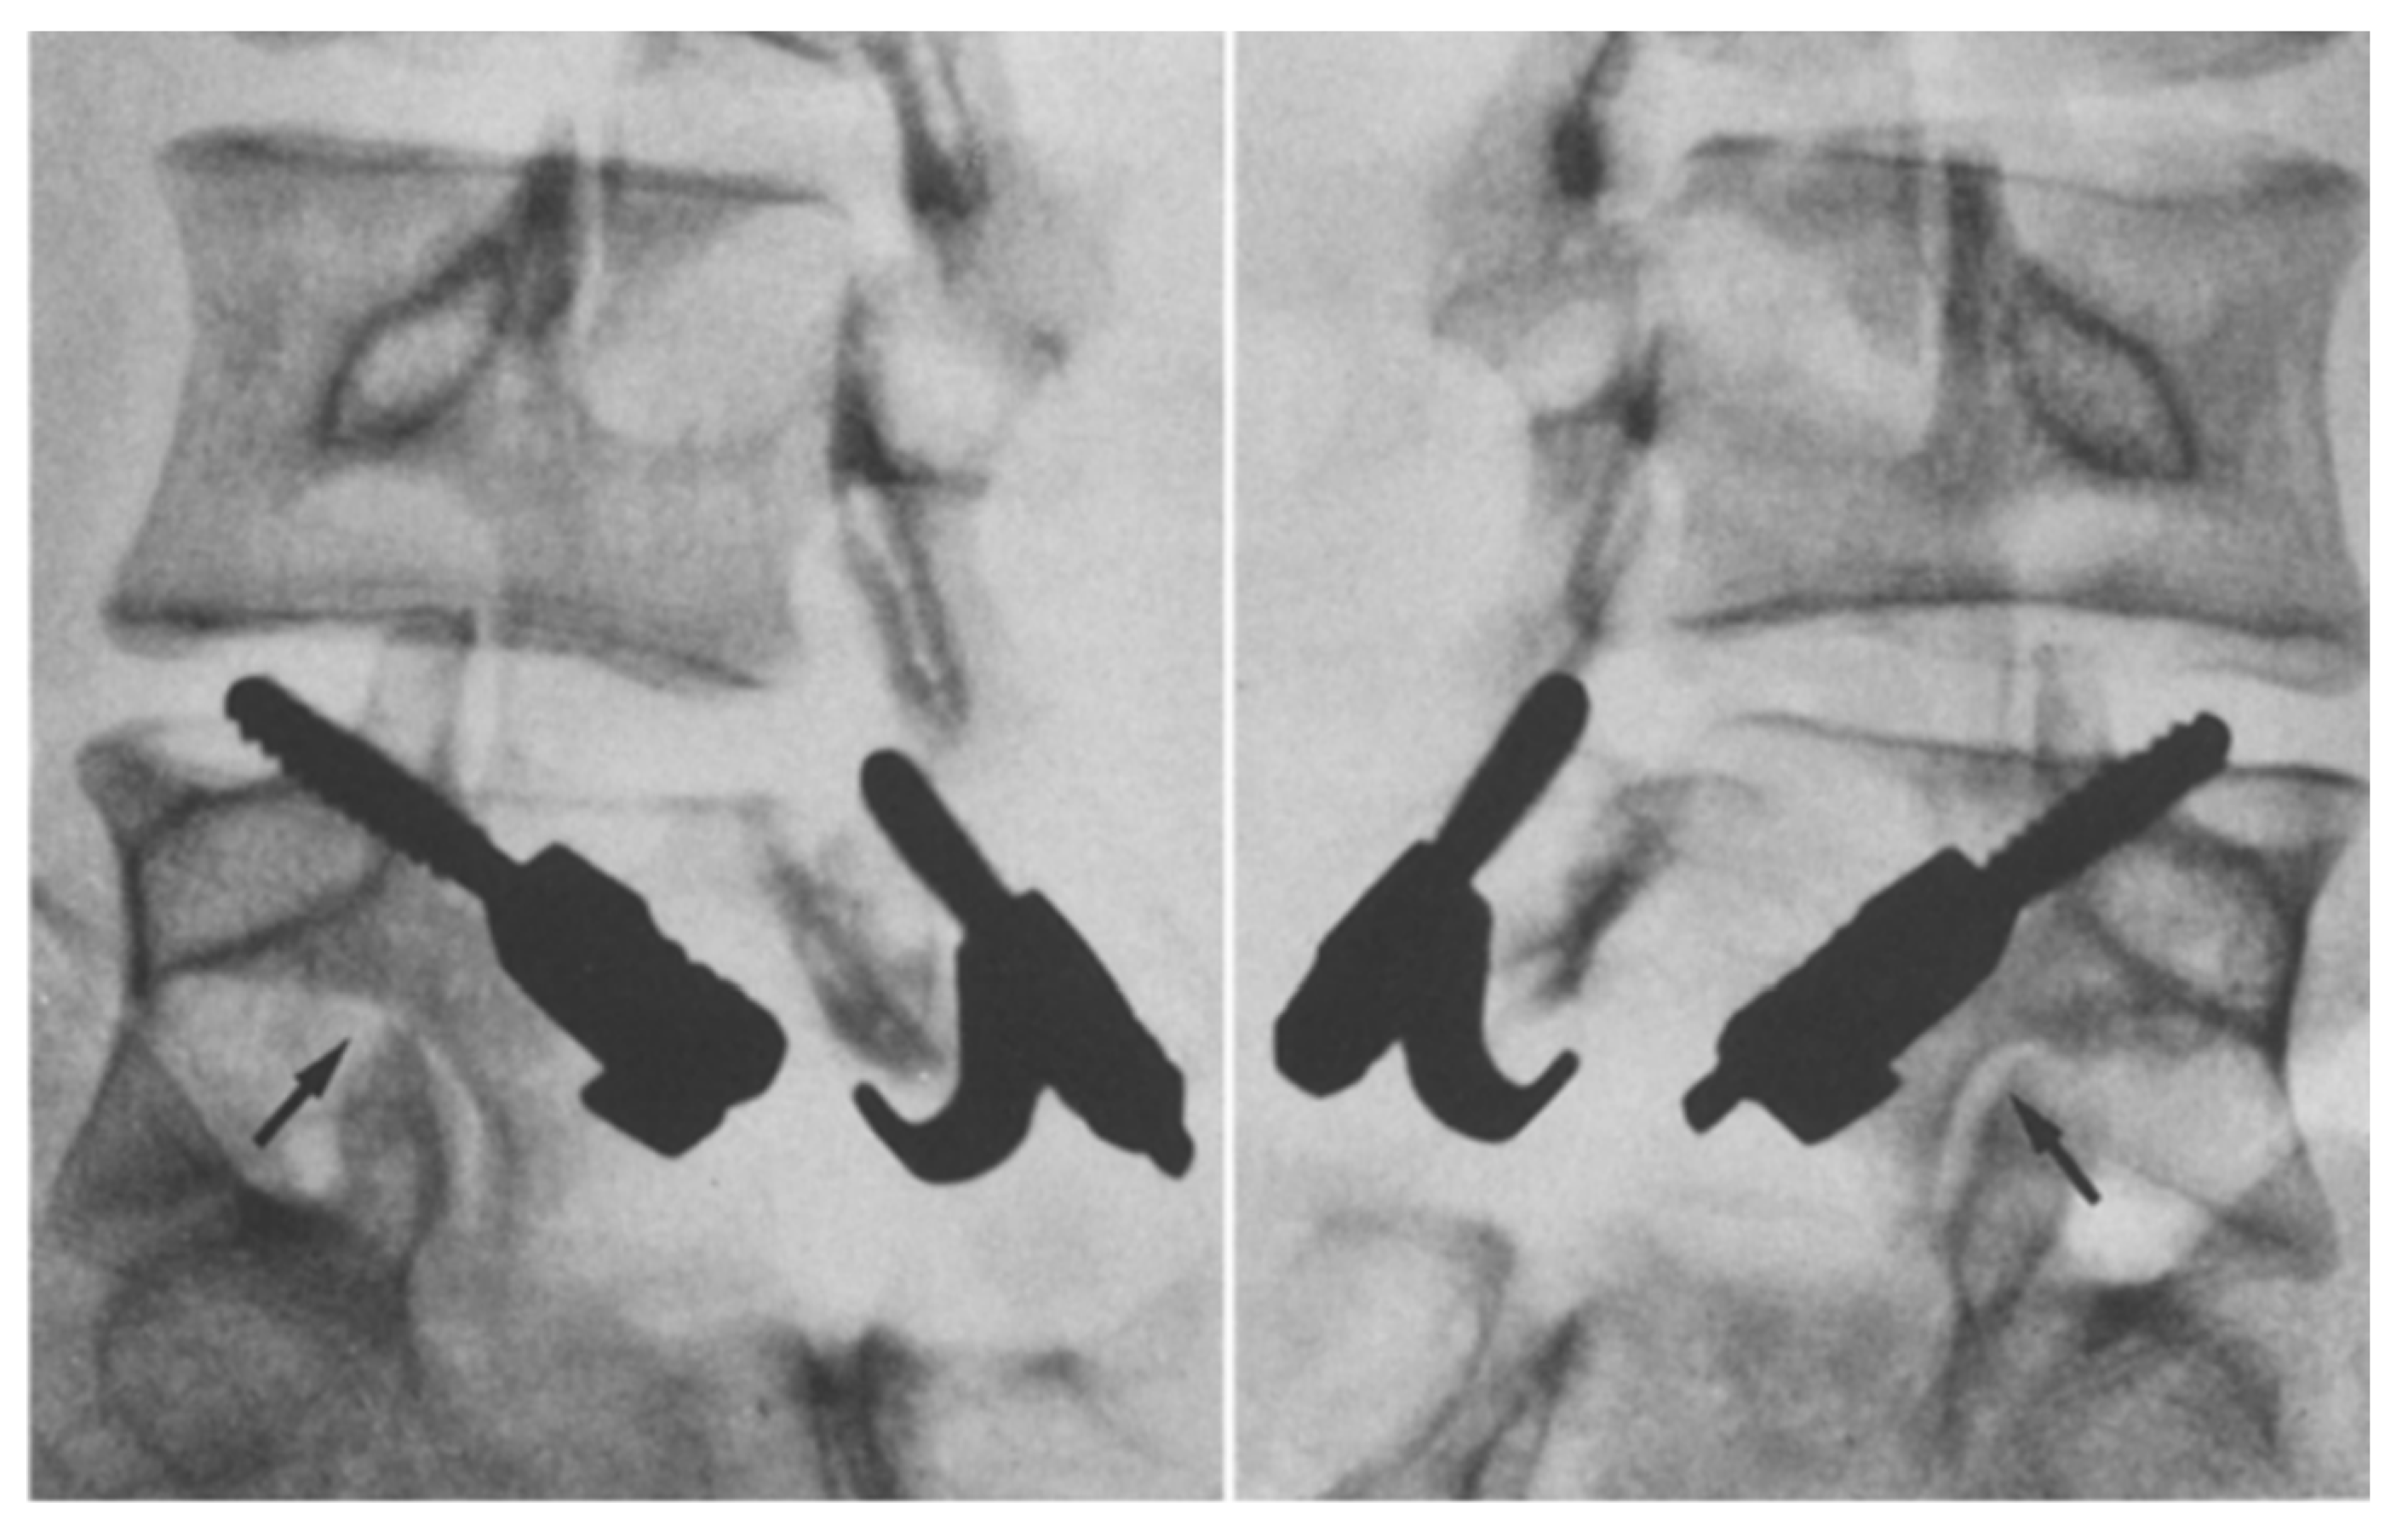

1.9.2. Morscher Screw-Hook Repair

- Hefti, F.; Seelig, W.; Morscher, E. Repair of lumbar spondylolysis with a hook-screw. Int. Orthop. 1992, 16, 81–85. [Google Scholar] [CrossRef]